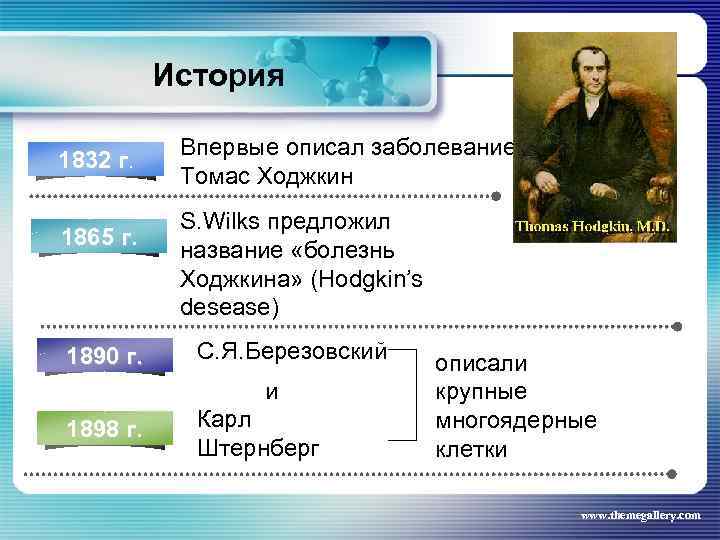

История 1832 г. 1865 г. 1890 г. Впервые описал заболевание Томас Ходжкин S. Wilks предложил название «болезнь Ходжкина» (Hodgkin’s desease) С. Я. Березовский и 1898 г. Карл Штернберг описали крупные многоядерные клетки www. themegallery. com

История 1832 г. 1865 г. 1890 г. Впервые описал заболевание Томас Ходжкин S. Wilks предложил название «болезнь Ходжкина» (Hodgkin’s desease) С. Я. Березовский и 1898 г. Карл Штернберг описали крупные многоядерные клетки www. themegallery. com